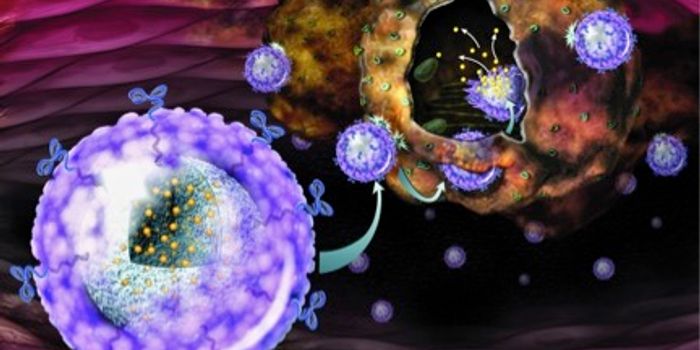

DEC 25, 2022CancerIn 1961, Jacques Miller discovered the function of the thymus, a lymphatic organ that houses important immune cells as t ...